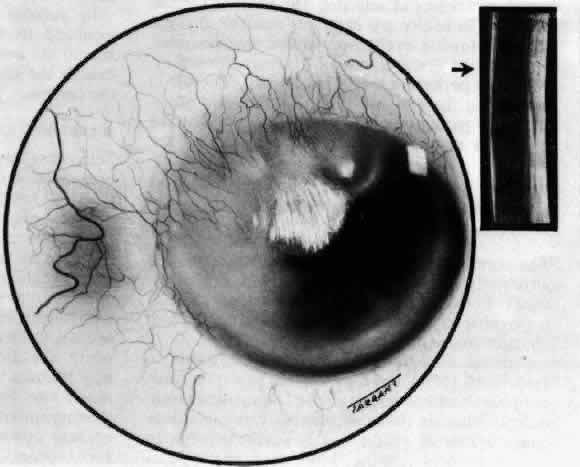

What is clinically represented solely by inflammation and edema is histopathologically

a granulomatous lesion of the sclera, the center of which

consists largely of plasma cells, lymphocytes, and mast cells (Figs. 21 through 23). Foster and colleagues have identified the cellular subsets and glycoproteins

that would lead to granuloma formation. Remote from the granuloma, the

fibrocytes of the sclera become activated, the proteoglycan adjacent

to them becomes altered, and the collagen fibrils of the sclera

become unraveled (Figs. 23 and 24). These changes appear to take place prior to the invasion of the stroma

collagen remote from the site of cellular infiltration.  Fig. 21. Advancing edge of a granulomatous reaction. Scleral fibers are split and

separated by edema and then disrupted when invaded by the granuloma Fig. 21. Advancing edge of a granulomatous reaction. Scleral fibers are split and

separated by edema and then disrupted when invaded by the granuloma

|